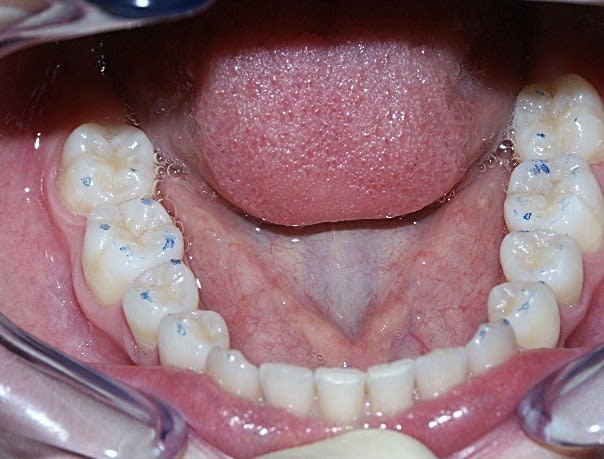

Avec l'arrivée des photos des moulages initiaux, je me suis dit" est ce le même cas", car:

avec la présentation du sujet (debut novembre)on parlait de classe III avec menton en galoche et en fait il semble qu'il y avait une grosse supra avec belle déviation à gauche et inversé d'articulé gauche.

Le trt ortho a du ramener la mand vers la droite mais comme le max n'est pas assez large la branche montante D remonte en Ar et le condyle vient compresser sa zone de réception.Il me semble donc qu'il faille bien augmenter la dimension transversale du max et la dv surtout à droite pour bloquer ce condyle droit dans sa course.J'avoue que c'est complexe mais elle ne doit pas être bien (cf photos),alors il faut faire qq chose.

bon je vous laisse encore quelques photos pour que vous puissiez argumenter la discussion.

- Modèles : très belle supraclusion antérieure et infragnatie organiques latérales. Donc, très belle DSD magistrale et ou il ne reste plus qu'à appliquer ce qui est écrit supra.